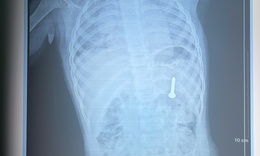

Nội soi gắp dị vật là vòng bạc trong dạ dày bé gái 5 tuổi

Y tế - 09/10/2025 18:30SKĐS - Mới đây, Bệnh viện Việt Nam – Thụy Điển Uông Bí tiếp nhận và xử trí thành công trường hợp trẻ 5 tuổi nuốt phải dị vật là chiếc vòng tay bằng bạc, dài khoảng 7 cm.